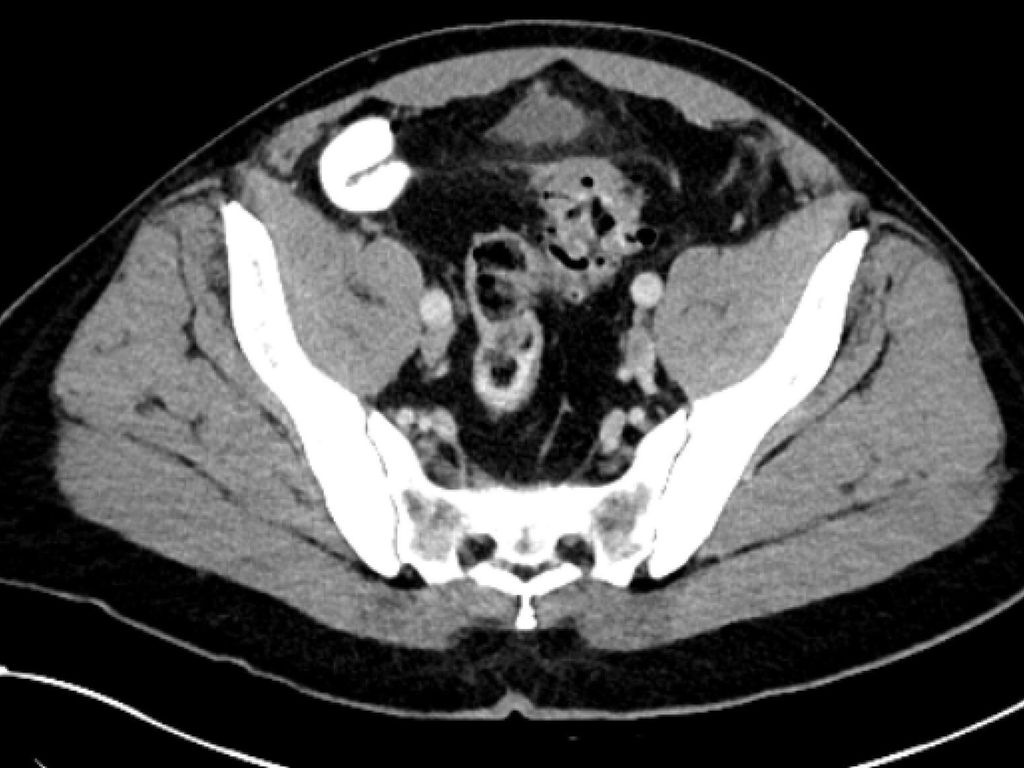

maladie diverticulaire/diverticulite simple aiguë (type 1a–b) (Fig. 1),

diverticulite compliquée aiguë (type 2a–c) (Fig. 2 et 3) et

maladie diverticulaire chronique (maladie diverticulaire symptomatique récidivante ou persistante; type 3a–c) (Fig.4).

Pour la classification de la diverticulite sigmoïdienne, la «Classification of Diverticular Disease» (CDD) s’est imposée (Tab. 1). Celle-ci a pour but de recueillir les différentes évolutions indépendamment d’une opération ainsi que de stratifier les différents pronostics et options thérapeutiques lors du premier diagnostic ou en cas de récidive. Une distinction est faite entre les formes suivantes:

La diverticulite compliquée aiguë de type 2 distingue, avec les types 2a et 2b, la perforation couverte avec micro-abcès (≤3cm) et macro-abcès (>3cm). Le type 2c désigne la perforation libre avec péritonite purulente ou fécale. La diverticulite compliquée aiguë nécessite une hospitalisation et doit être traitée par une antibiothérapie. Si l’apport en liquides est insuffisant, il convient de substituer les liquides par voie parentérale. Un apport alimentaire adapté à la situation peut être mis en place. Contrairement au macro-abcès de type 2b, le micro-abcès de type 2a n’est pas accessible au drainage interventionnel. Si le traitement est efficace, il n’y a pas forcément d’indication d’une opération élective. Il convient de noter que le risque de récidive est corrélé à la taille de l’abcès. Les abcès rétropéritonéaux ou péricoliques (>3cm) peuvent faire l’objet d’un drainage interventionnel. Après une thérapie conservatrice ou interventionnelle réussie de la diverticulite, une opération peut être proposée dans l’intervalle sans inflammation, après environ 6 semaines.